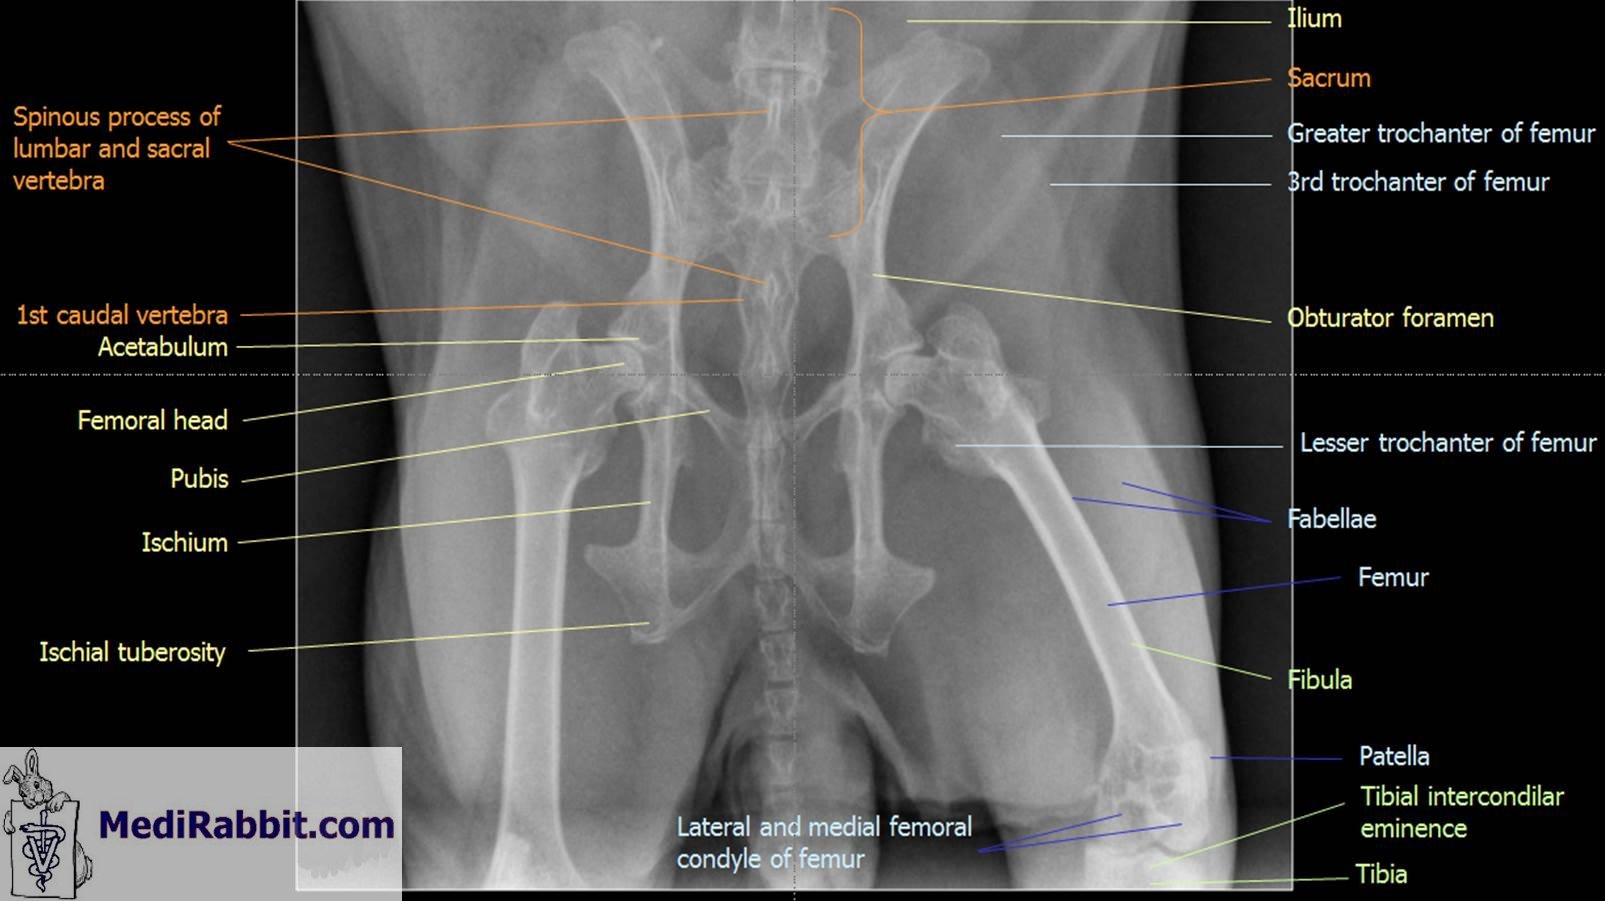

Radiography of the hip

Dorso-ventral view view

Kim Chilson